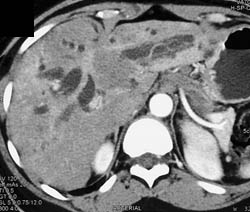

Liver Abscess